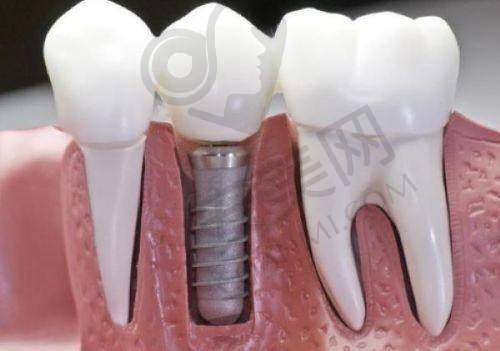

曾经有一位55岁因牙周病缺单颗后牙的顾客找到他。他并没有急于种牙,而是先帮顾客控制牙周炎症。因为如果牙周炎症没有得到控制就进行种牙,可能会影响种植体的稳定性和成功几率。在控制好炎症后,他为顾客选择了韩国登腾种植体。在种牙过程中,他调整种植角度,让种植体更加稳固。术后2个月,顾客就能正常使用种植牙了。